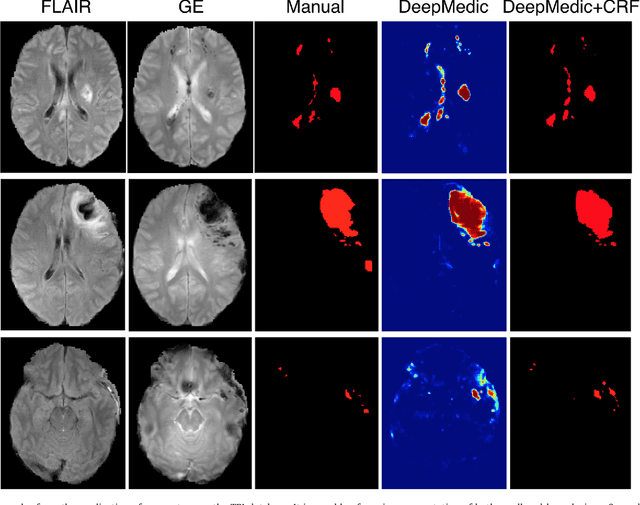

We propose a dual pathway, 11-layers deep, three-dimensional Convolutional Neural Network for the challenging task of brain lesion segmentation. The devised architecture is the result of an in-depth analysis of the limitations of current networks proposed for similar applications. To overcome the computational burden of processing 3D medical scans, we have devised an efficient and effective dense training scheme which joins the processing of adjacent image patches into one pass through the network while automatically adapting to the inherent class imbalance present in the data. Further, we analyze the development of deeper, thus more discriminative 3D CNNs. In order to incorporate both local and larger contextual information, we employ a dual pathway architecture that processes the input images at multiple scales simultaneously. For post-processing of the network's soft segmentation, we use a 3D fully connected Conditional Random Field which effectively removes false positives. Our pipeline is extensively evaluated on three challenging tasks of lesion segmentation in multi-channel MRI patient data with traumatic brain injuries, brain tumors, and ischemic stroke. We improve on the state-of-the-art for all three applications, with top ranking performance on the public benchmarks BRATS 2015 and ISLES 2015. Our method is computationally efficient, which allows its adoption in a variety of research and clinical settings. The source code of our implementation is made publicly available.